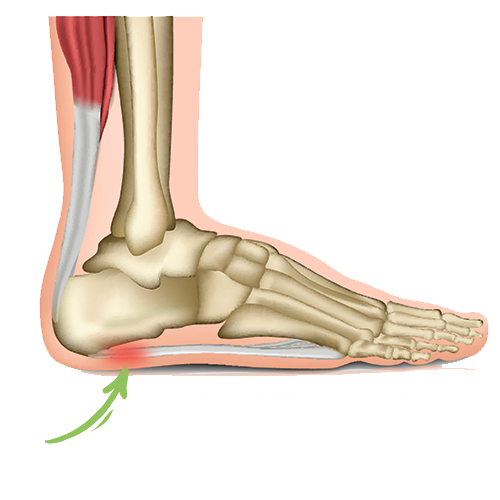

- Hælspore